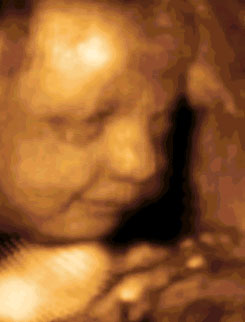

Quando spunta il primo dentino?

I denti sono già tutti presenti nella bocca del bambino al momento della sua nascita, perché si formano quando il bimbo è ancora nel pancione. Il primo dentino spunterà però solo dopo qualche tempo, ovvero tra il sesto e l'ottavo mese. ...